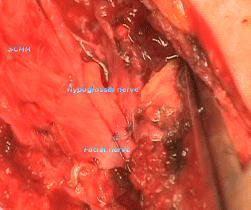

The left hypoglossal nerve was exposed and the left facial nerve was drilled off the canal for 10 mm depth and the hypoglossal nerve was sharply cut just before the emergence of the ansa cervicalis. It was rotated upward and direct anastamoses was performed between the 2 nerves.

Fig.-1: The anatomical relationship of the facial and hypoglossal nerves.

Fig-2: The anastamosis performed.        Fig-3: The tip of mastoid returned.